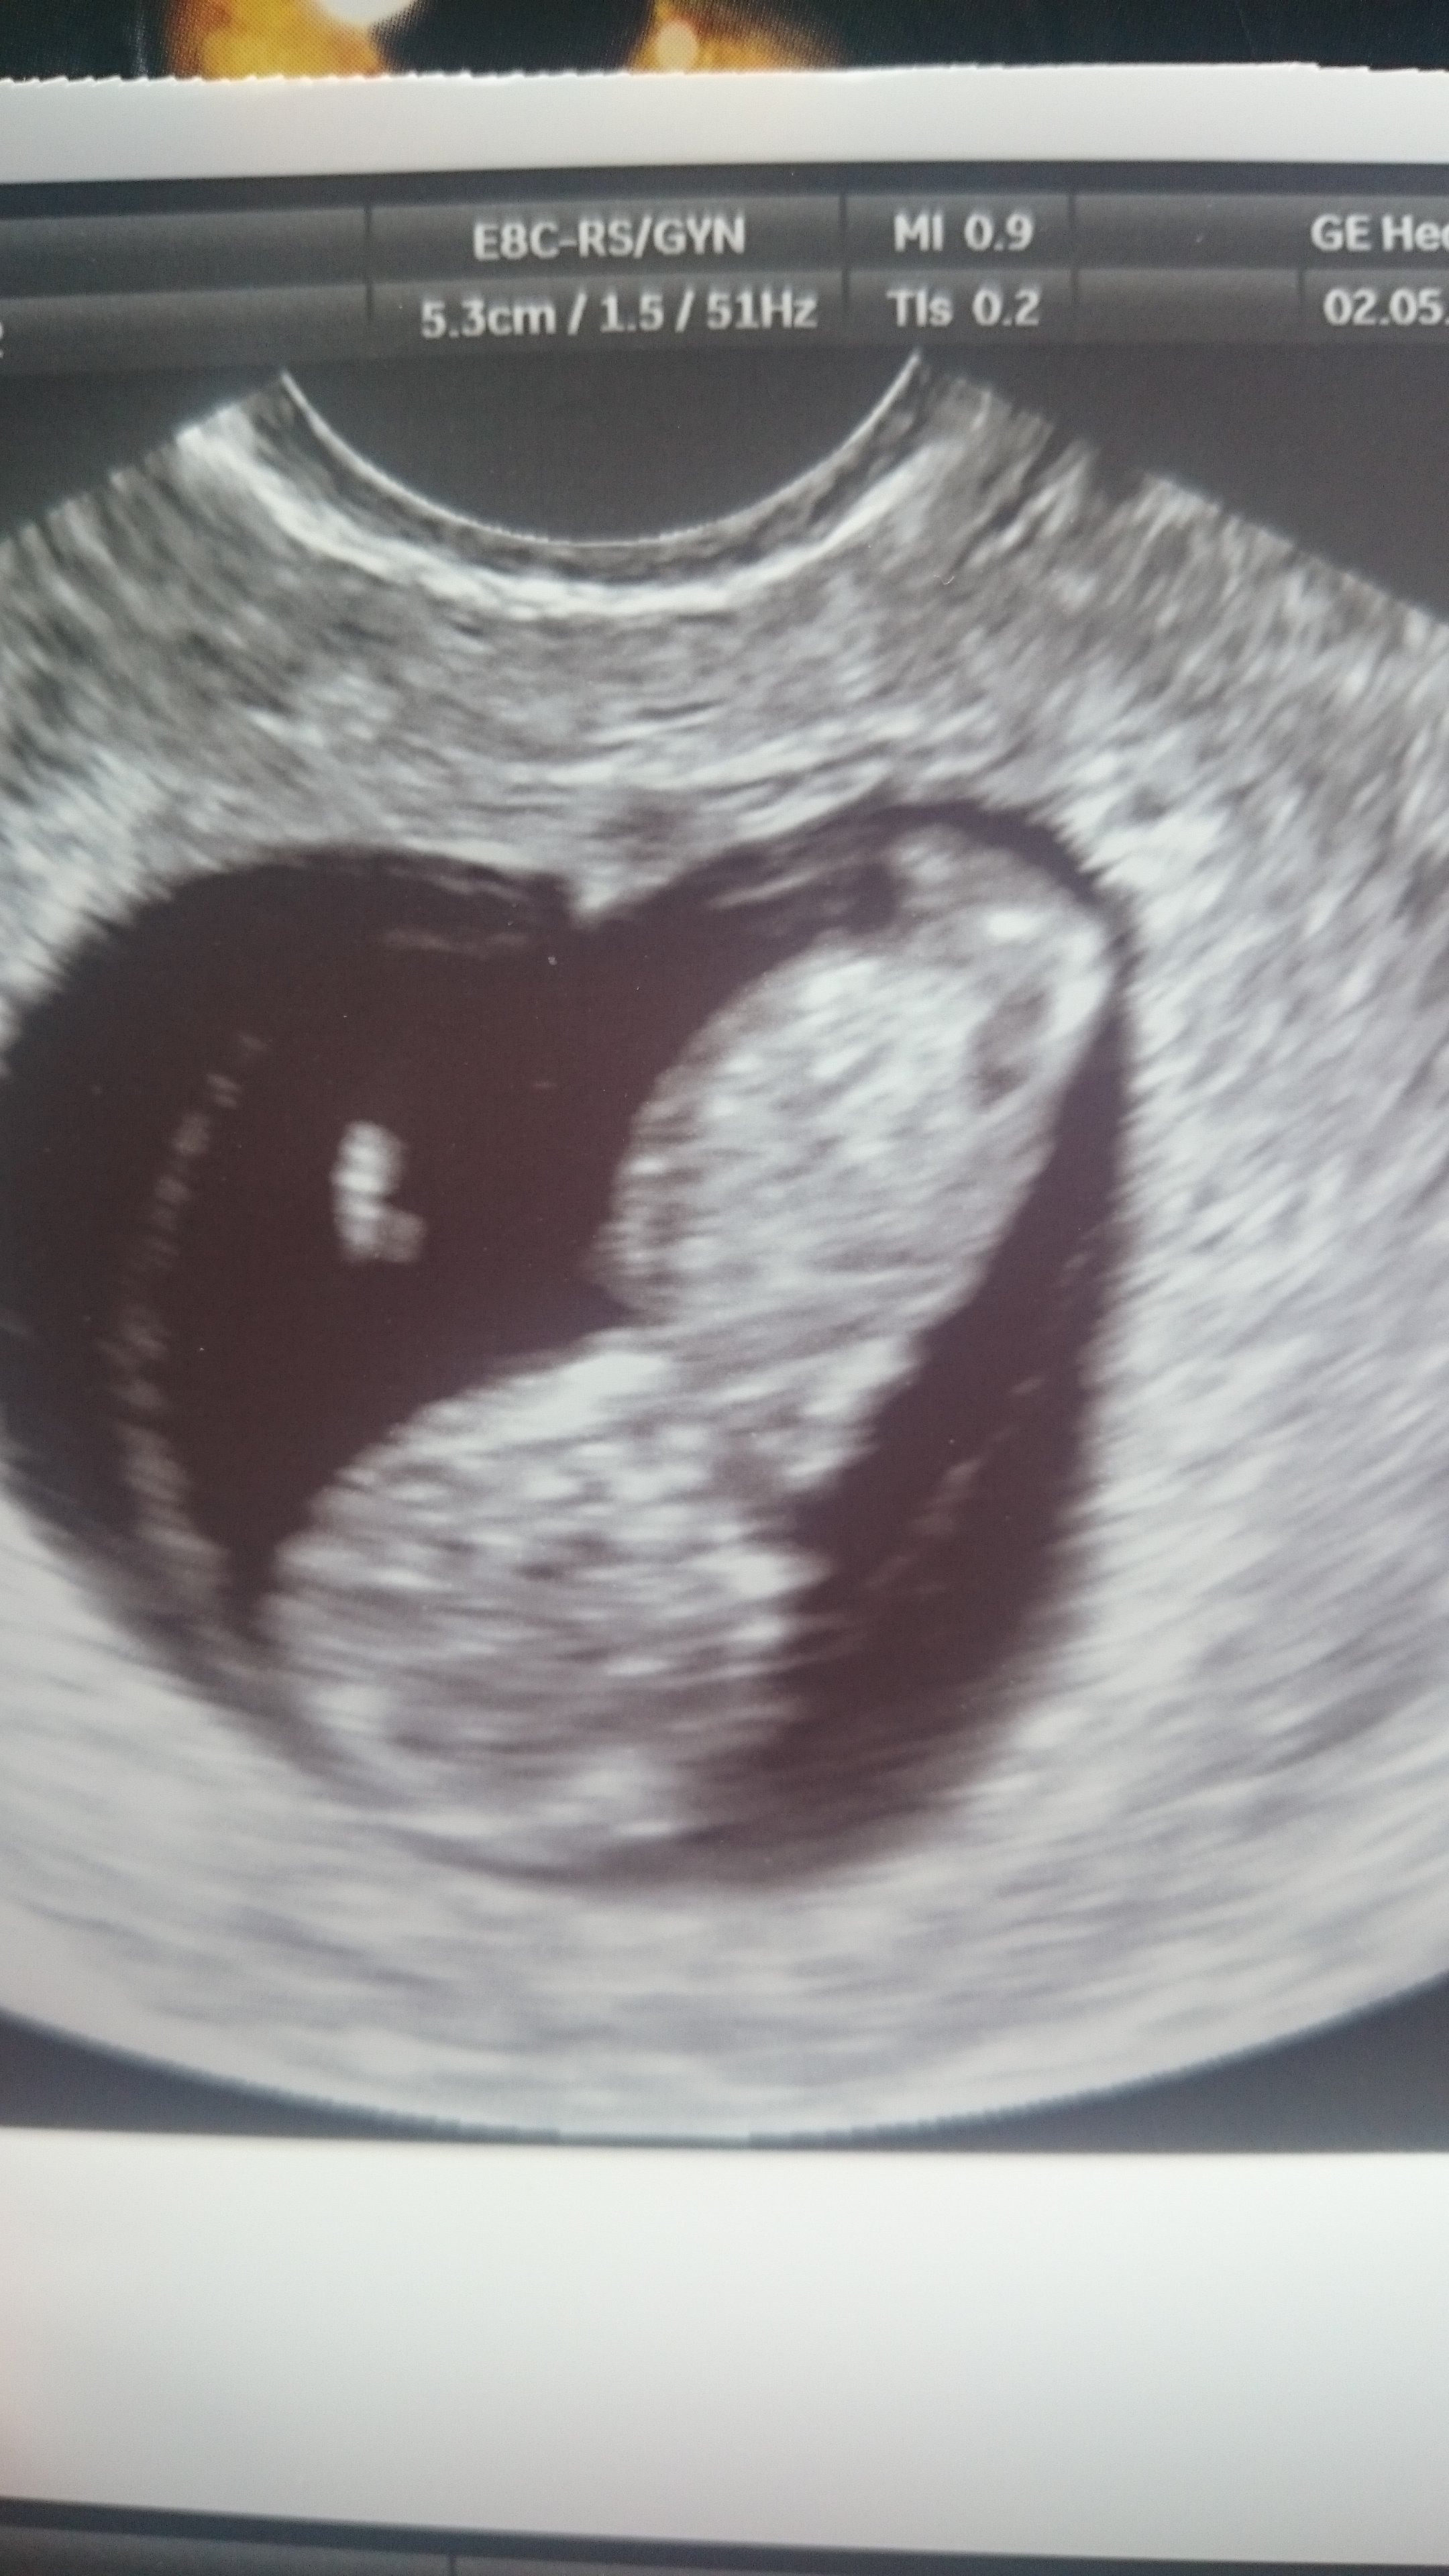

Super dzidzia gratulacje☺Zobacz załącznik 804782 Zobacz załącznik 804783 Zobacz załącznik 804784

My po wizycie

Na pierwszym zdjęciu widać rączkę, na drugim rączki, nóżki, na trzecim jest do góry nogami. Ruszał się, wręcz tańczył, serduszko tłucze jak szalone. Wszystko jest pięknie! Lekarz zachwycony, a my przeszczęśliwi![]()